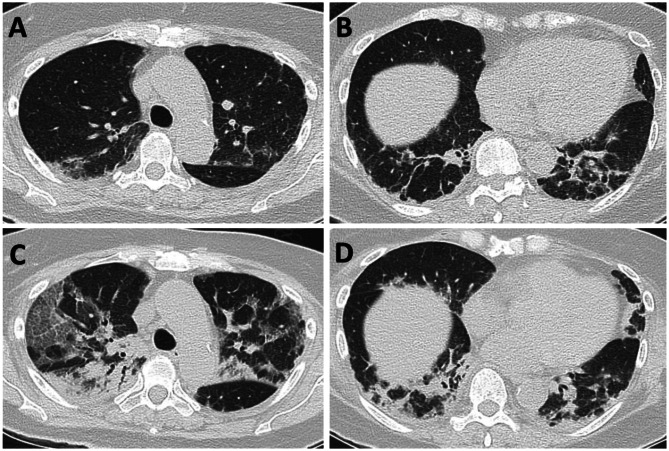

Clinical characteristics and outcomes of anti-MDA5 dermatomyositis: a retrospective study.